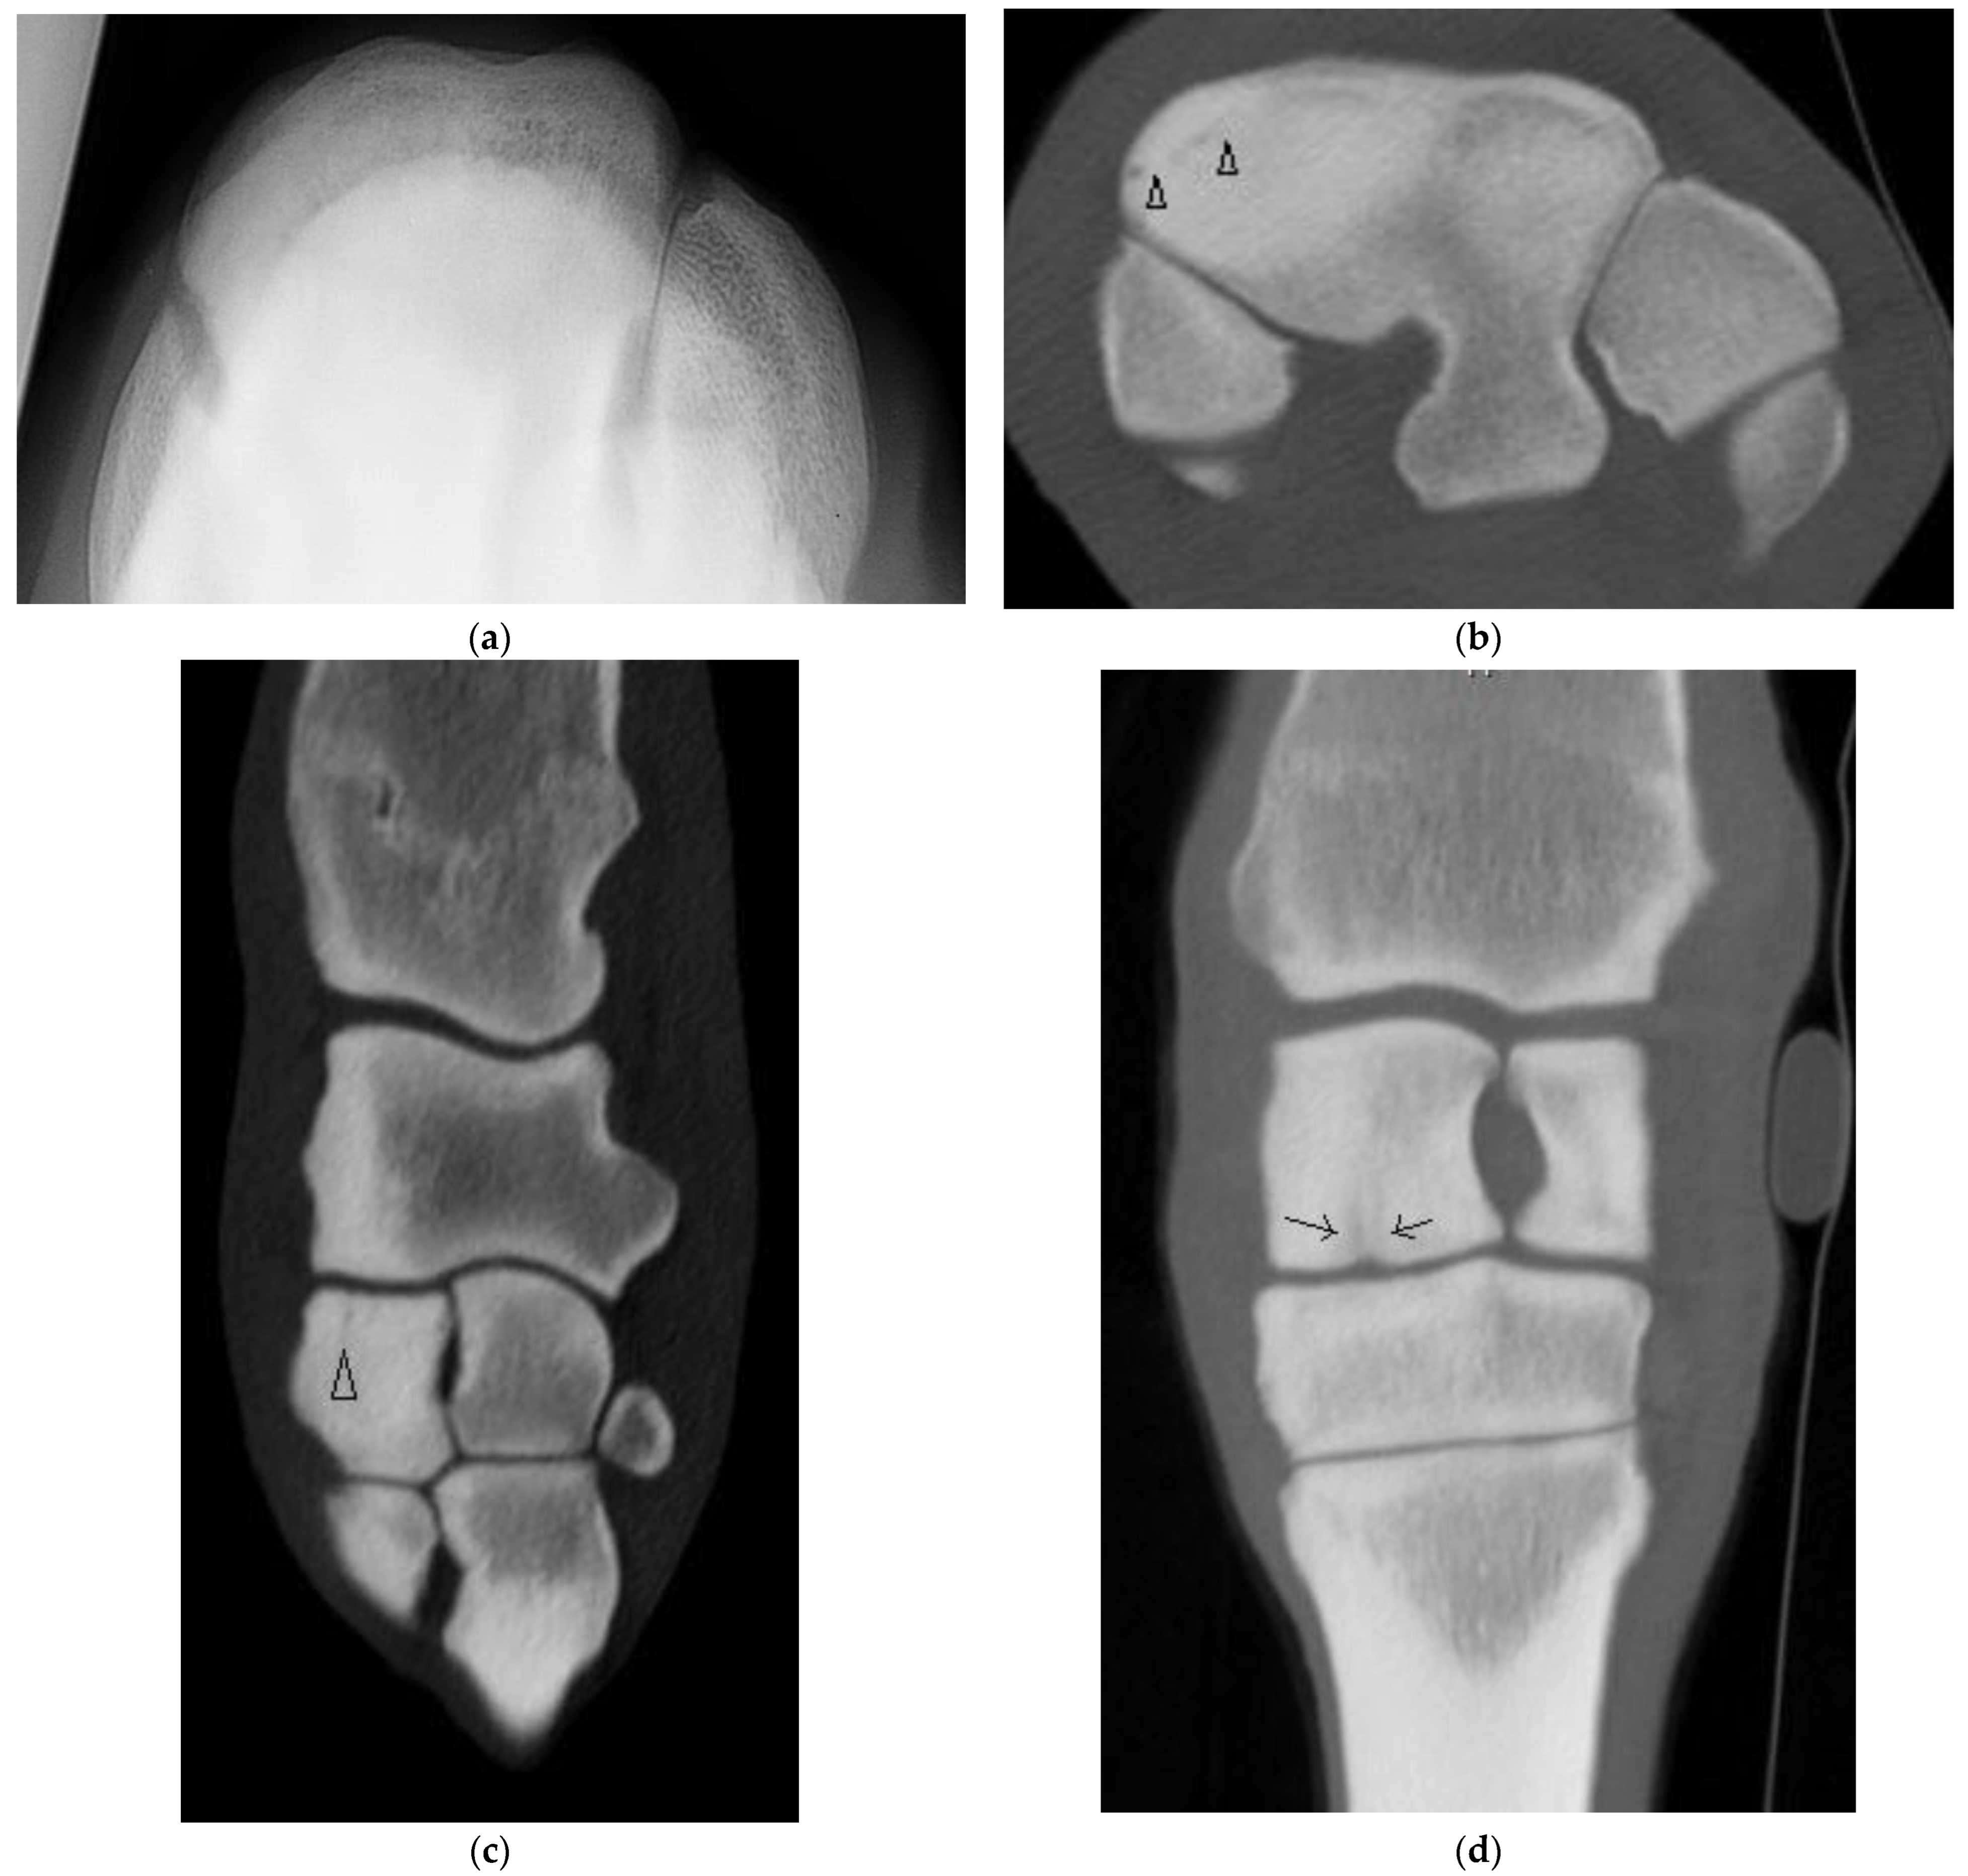

Four horses had complete fractures of variable configuration with both sagittal and frontal components. Three were corner Fx of the RaF and two of these had substantial additional fissures or fractures detected only on CT (Figure 4). The other horse had a complete Fx of both facets, with orientation that was sagittal in the RaF and frontal palmar to the InF (Figure 5); a configuration not recognized on DR.

Figure 5. Images of the right carpus of a 3-year-old standardbred filly. (a) Flexed dorsoproximal-dorsodistal oblique radiographic view of the distal row of carpal bones. There is a vague sagittal lucency surrounded by sclerosis within the radial facet (RaF) of the third carpal bone (C3). A fracture was suspected but the configuration was unclear. (b) Transverse CT image through proximal C3. CT imaging confirmed a complete slab fracture of C3 that is sagittal within the RaF then courses in a frontal plane palmar to the intermediate facet (arrow heads). The fracture passes through a moderate sized subchondral lucency within the RaF.